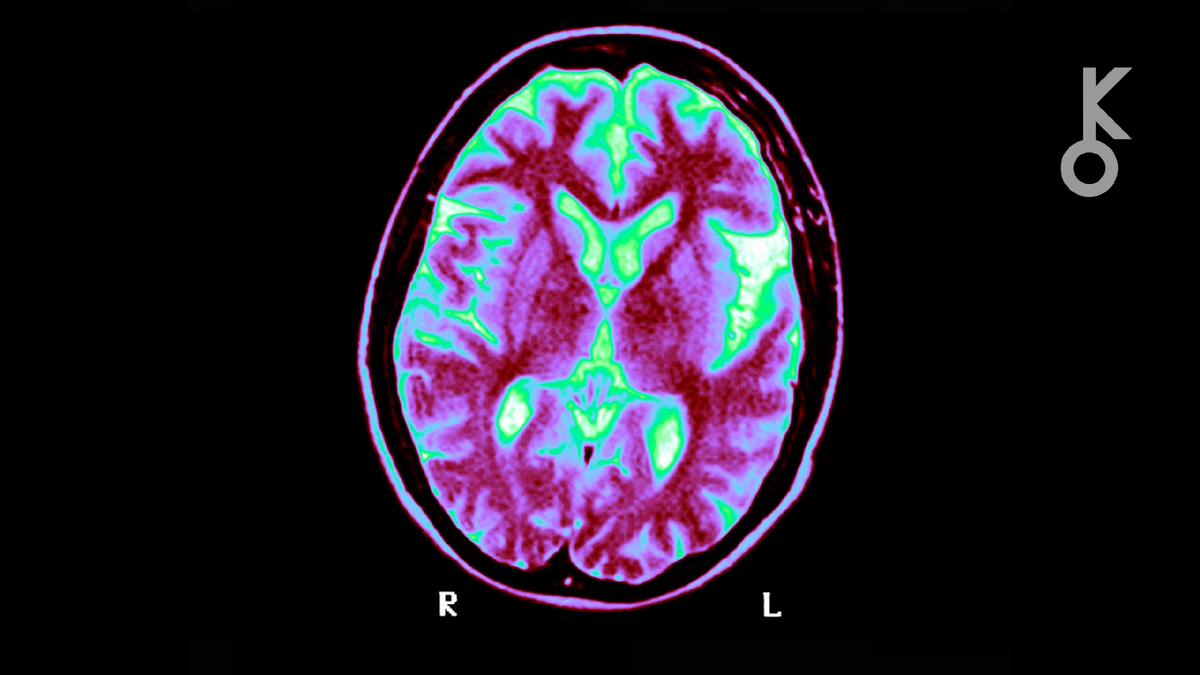

Сахар и мозг: новое открытие меняет взгляд на нейробиологию

Ученые выяснили, что нейроны перерабатывают сахар иначе, чем считалось. Это открытие может стать ключом к лечению болезней Альцгеймера и Паркинсона.

Наш мозг — невероятно энергозатратный орган. Потребляя почти четверть всей глюкозы в организме, он постоянно нуждается в «топливе» для поддержания своей сложной деятельности. Долгое время в научном сообществе доминировала теория о том, что основную работу по переработке сахара выполняют глиальные клетки, которые, словно заботливые помощники, снабжают нейроны энергией. Однако недавние исследования полностью переворачивают эти представления, указывая на то, что нейроны сами активно участвуют в метаболизме глюкозы, и этот процесс имеет решающее значение для здоровья мозга.